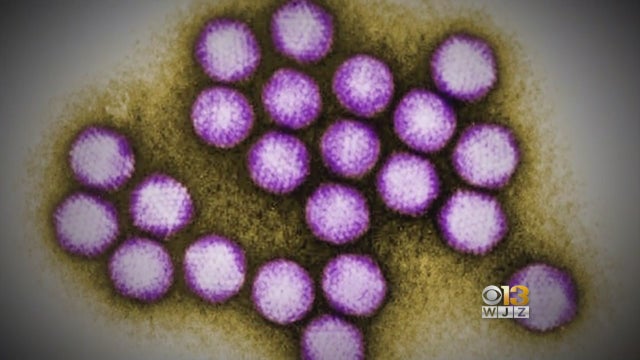

Concern about an outbreak of coronavirus in the US comes as Maryland lawmakers advance a bill that stems from an outbreak of a different virus at the University of Maryland in 2018.